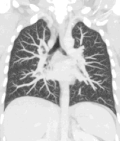

A CT scan can be used for detecting both acute and chronic changes in the lung parenchyma, the tissue of the lungs.[41] It is particularly helpful because normal two-dimensional X-rays do not show such defects. A variety of techniques are used, depending on the suspected abnormality. For evaluation of chronic interstitial processes such as emphysema, and fibrosis,[42] thin sections with high spatial frequency reconstructions are used; often scans are performed both on inspiration and expiration. This special technique is called high resolution CT that produces a sampling of the lung, and not continuous images.[43]

HRCT images of a normal thorax in axial, coronal and sagittal planes, respectively.